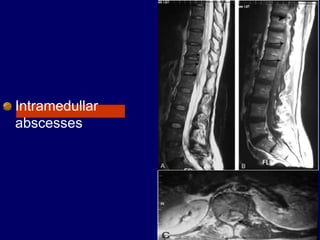

Intramedullar

abscesses